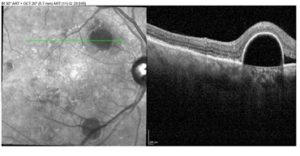

Although asymptomatic patients with PED that spares the fovea can be monitored without treatment, the retinal specialist consulted in this case recommended a monthly series of anti-VEGF injections for the right eye due to the associated SRF. The presence of SRF was suggestive of underlying RPE decompensation that allowed fluid entry into subsensory space, which placed the patient at higher risk for visual compromise.10 Consequently, he was treated at his first and second follow-up visits, after which SRF in the right eye nearly completely resolved (Figure 4). The underlying PED also exhibited a reduction in height. During his last scheduled injection appointment, however, recurrence of SRF over the superior PED was noted (Figure 5). Given re-emergence of SRF, the patient’s treatment schedule was altered from an original treat-and-extend regimen, which would have lengthened follow-up intervals to longer than one month, to two additional monthly injection visits.

![]() Figure 5. Optical coherence tomography scan showing recurrent subretinal fluid nasal to the superior pigment epithelial detachment after four anti-vascular endothelial growth factor injections. |